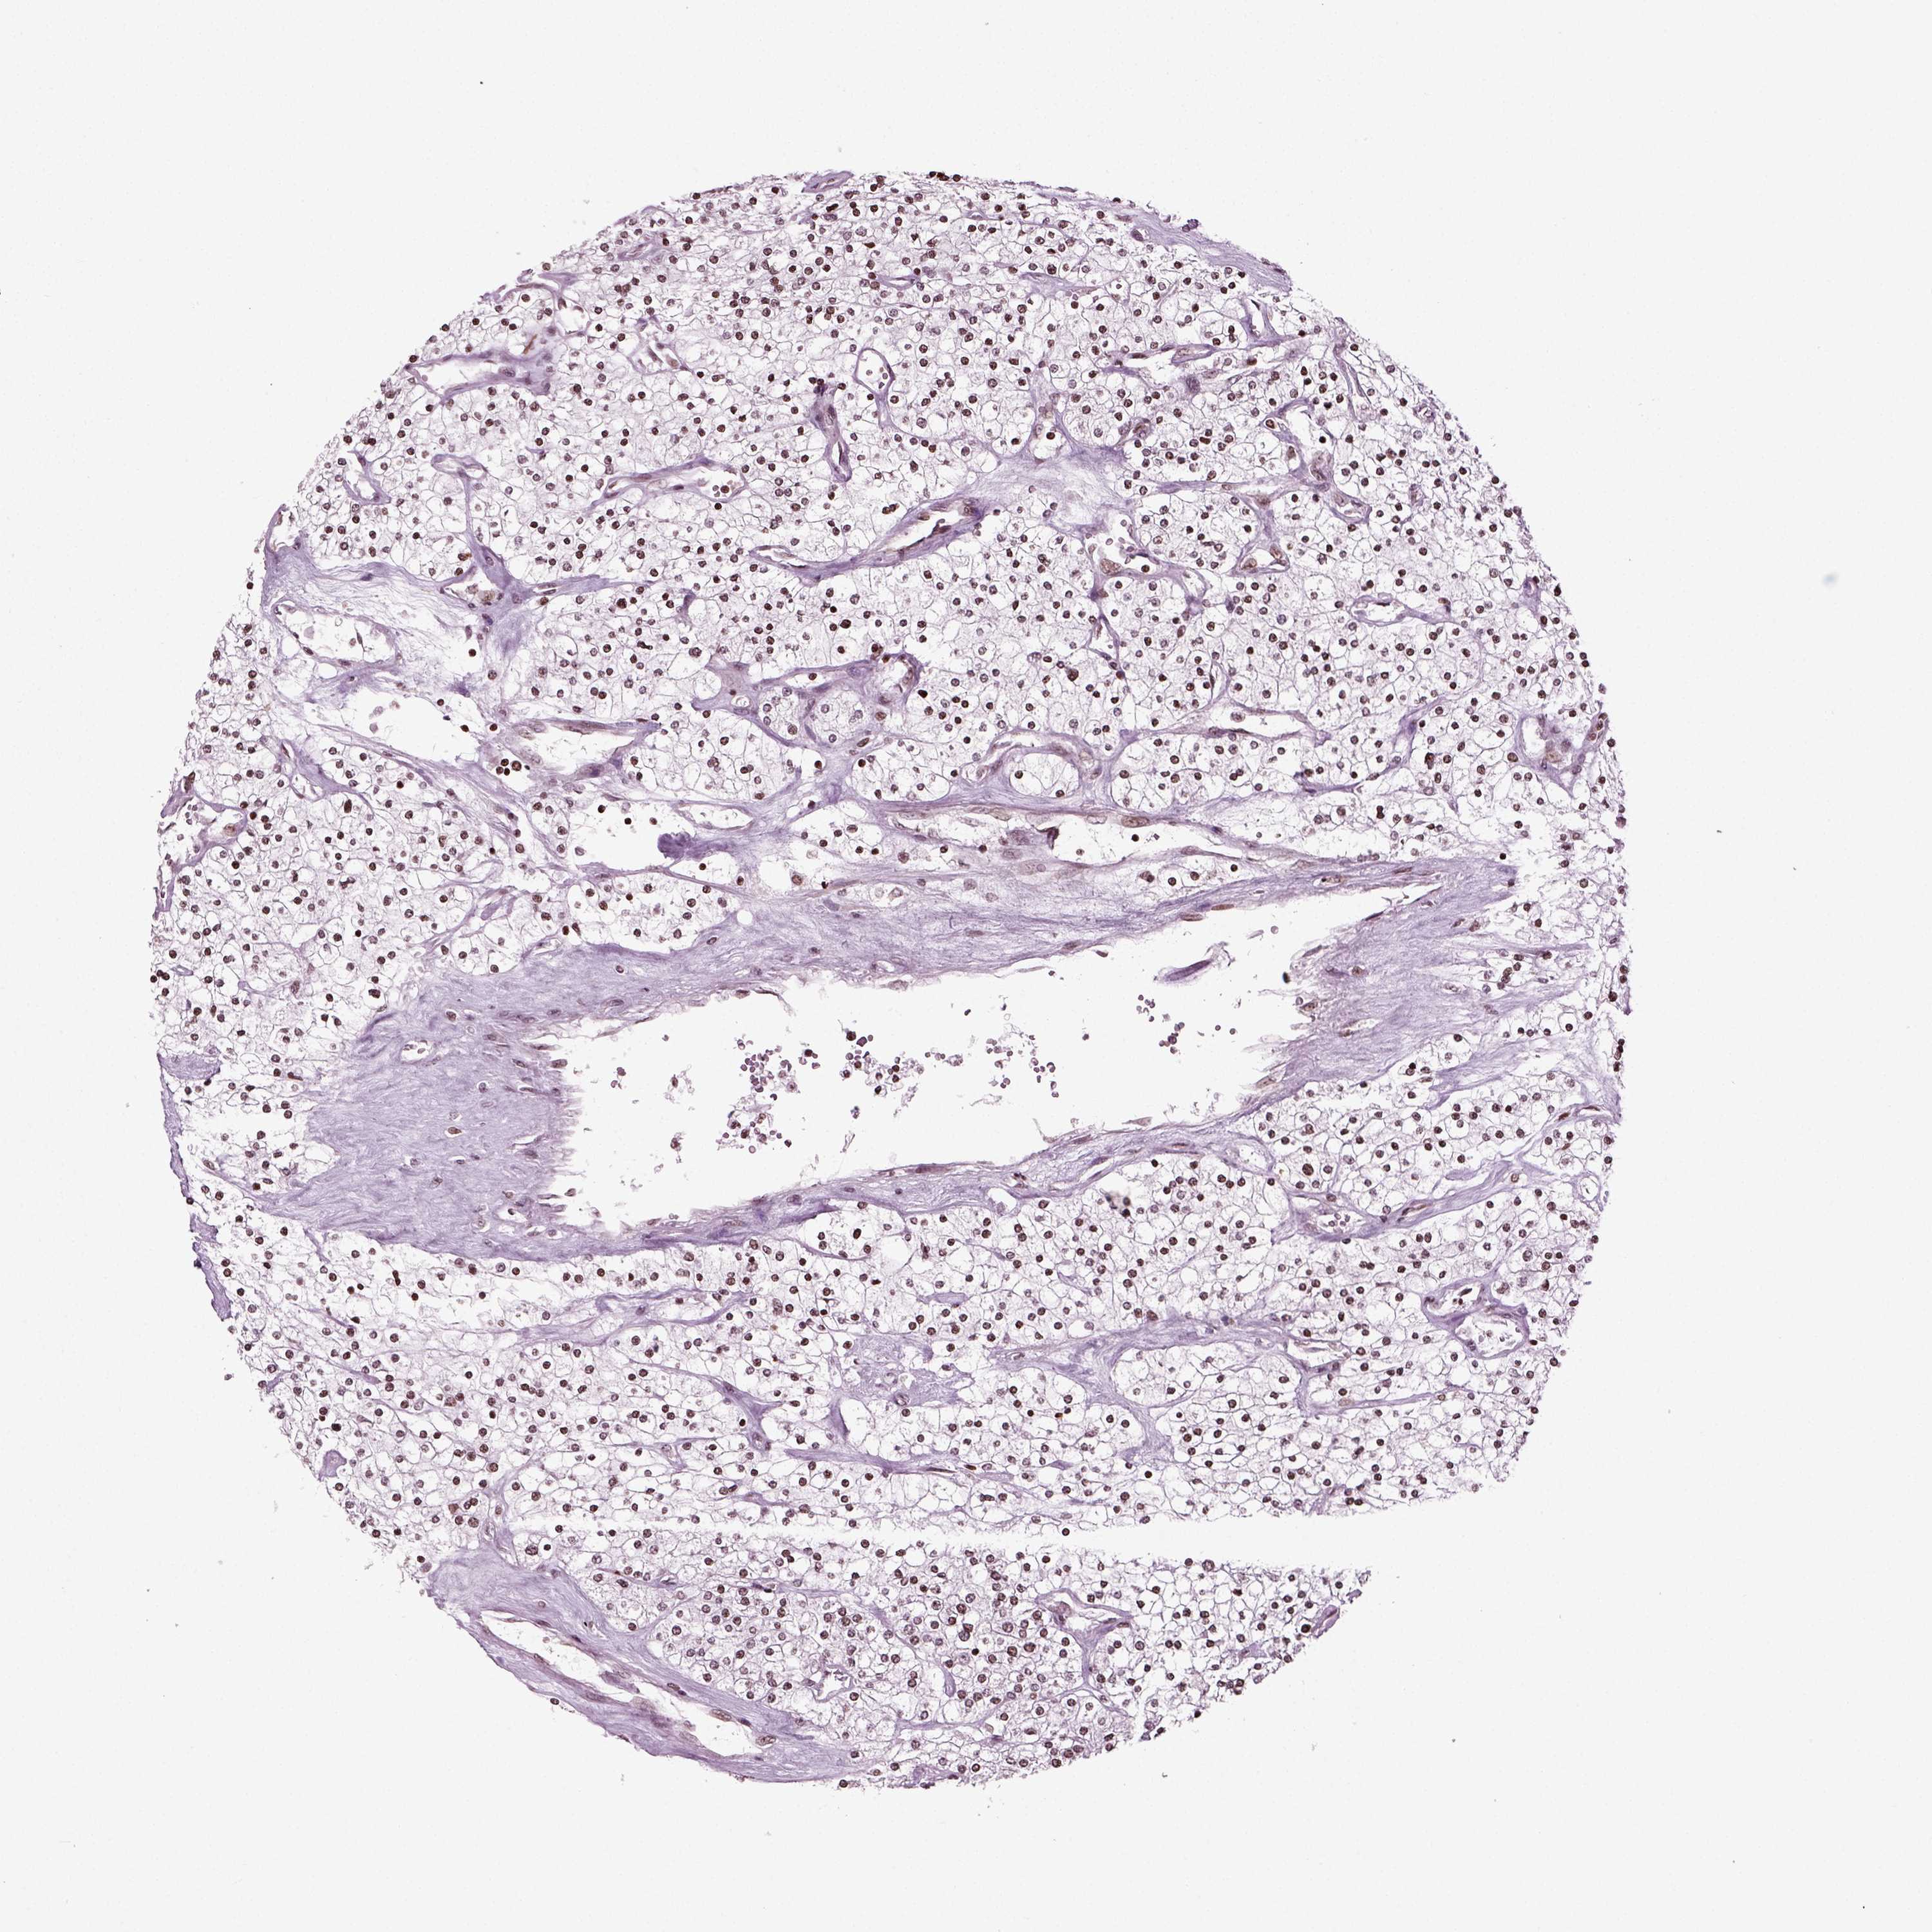

TCGA RNA samplesi

RNA-seq data is reported as average FPKM (number Fragments Per Kilobase of exon per Million reads), generated by the The Cancer Genome Atlas (TCGA) .

Normal distribution across the dataset is visualized with box plots, shown as median and 25th and 75th percentiles. Points are displayed as outliers if they are above or below 1.5 times the interquartile range. FPKM values of the individual samples are presented next to the box plot.

Average pTPM 33.1

Number of samples 521